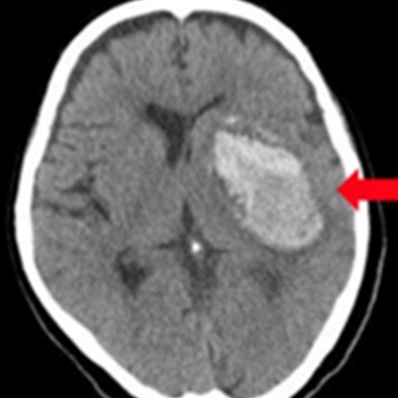

上から 急性硬膜下血腫、

脳挫傷、外傷性くも膜下出血

皮質下出血

被殻出血